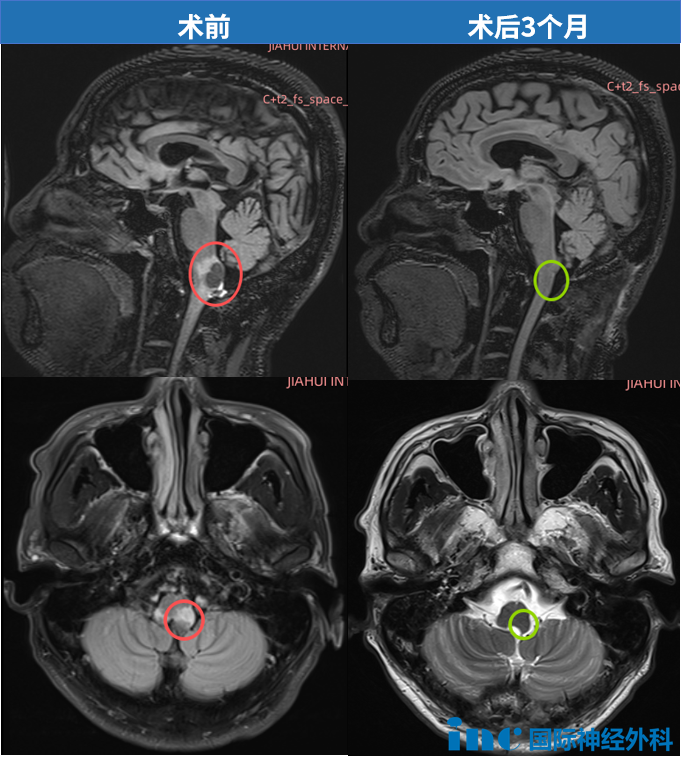

巴教授提到,术中神经电生理监测就像一个"扫雷器",能实时追踪各种神经电信号。在巴教授看来,没有电生理监测的脑外科手术是不人道的。业内有一句流行的话:监测本身很简单,复杂的是判断监测结果。巴教授在手术中"双肩挑"——一边全神贯注进行显微操作,一边在关键步骤主动询问监测数据的变化,这种模式让主刀医生能够在术中实时保护正常的神经功能。2025年8月13日,巴教授作为北京天坛医院神经外科外籍专家,经枕下正中入路,成功为W先生实施了延髓血管母细胞瘤全切手术。

07 术后恢复:回归热爱的生活